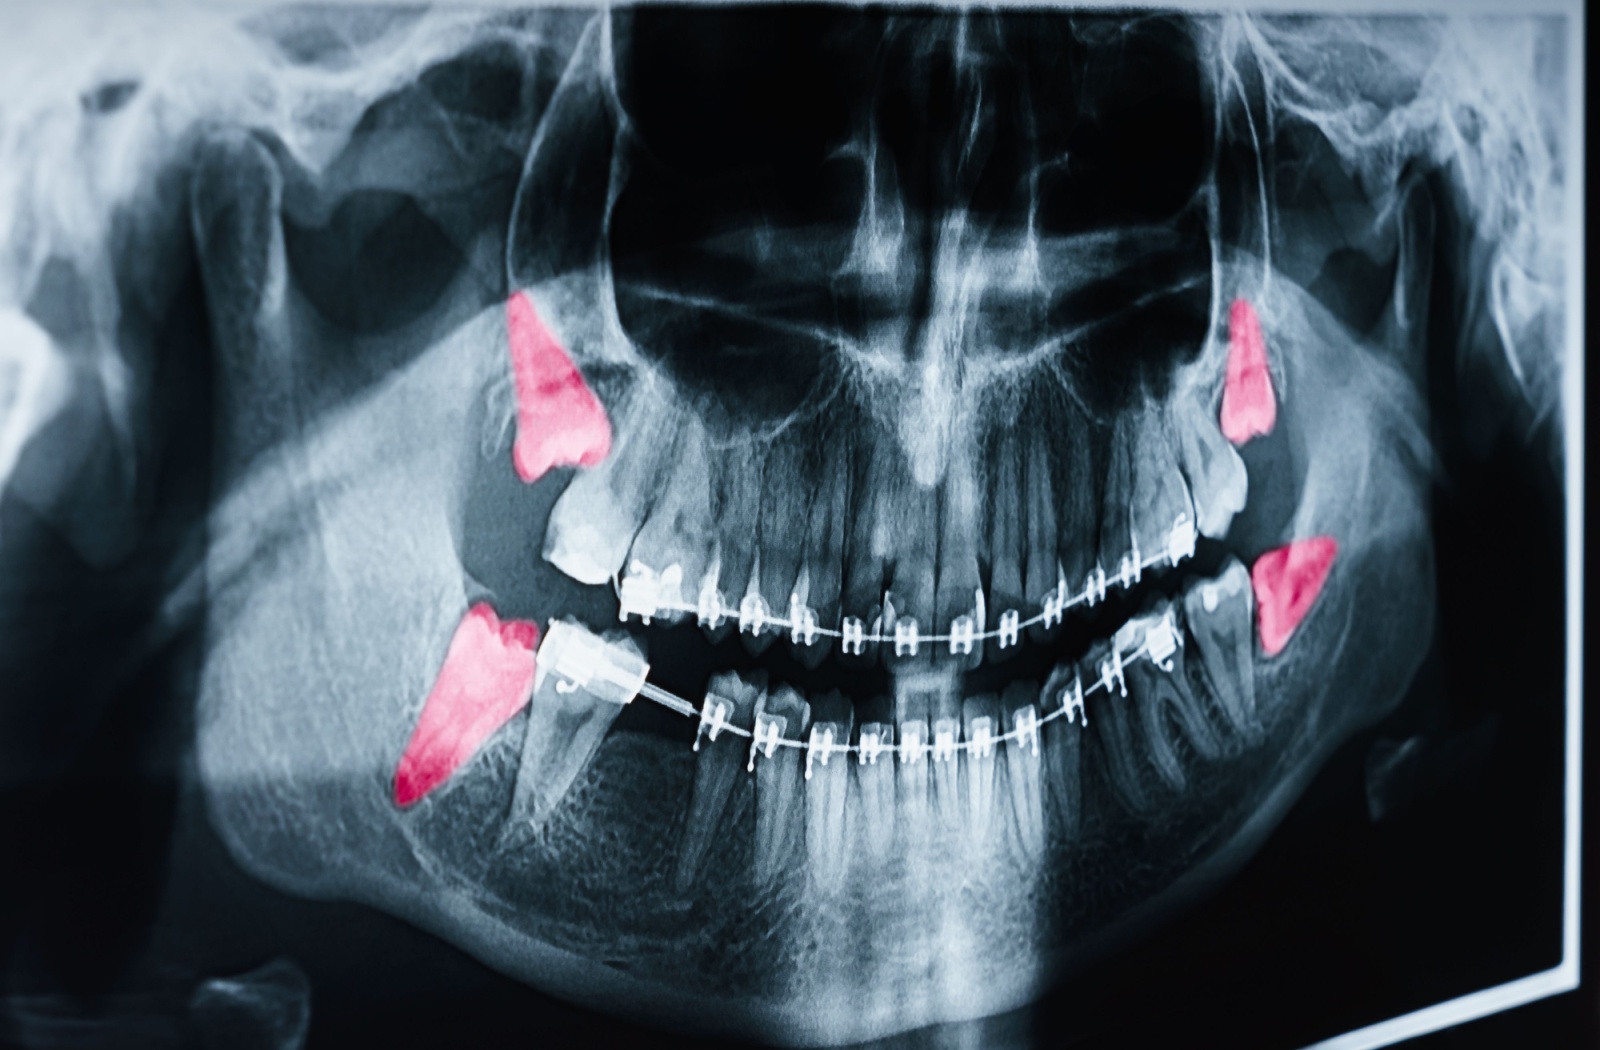

Wisdom teeth can be cantankerous additions to your gum line. If they are misaligned or impacted, these molars are likely to cause pain or even infection. If you are getting headaches, jaw aches, or having trouble opening your mouth entirely it may be a good idea to visit a dentist for their opinion on your situation.

- Cysts (this necessitates a dentist’s diagnosis)

- Cysts: A non-erupted wisdom tooth can develop a cyst along the jawline. This type of cyst can damage the bone in your jaw, as well as gum tissue.